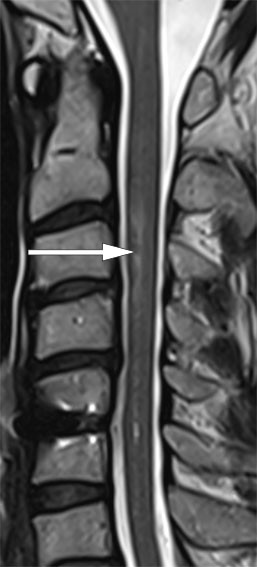

Brain MRI showed findings consistent with a small, recent infarction in the left cerebellum. There was now a more distinct, increased intramedullary T2 signal intensity at levels C2–C4 (Figure 1), with axial diffusion imaging showing restricted diffusion in areas with an increased T2 signal, predominantly at the left side (Figure 2).

Where there is a clinical suspicion of acute medullary infarction, a diffusion-weighted MRI scan should be performed, as T2 signal abnormalities may be subtle or absent early in the acute phase. At levels C3–C5, presentation of the medulla may be affected by various MRI artefacts, which can make it difficult to detect signal abnormalities.